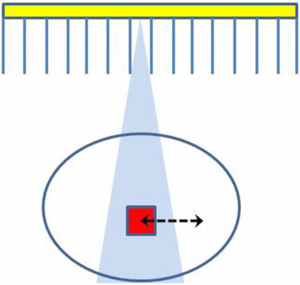

The three-dimensional (3D) distribution of a radioactive tracer inside a patient can be quantified using the functional imaging modalities of positron emission tomography (PET) and single photon emission computed tomography (SPECT). The accuracy of the quantification is limited, however, due to the relatively poor spatial resolution achievable with these modalities. Spatial resolution-related effects are usually referred to as 'partial volume effects' (PVEs). In general the partial volume effect can be defined as the loss in apparent activity that occurs when an object partially occupies the sensitive volume of the imaging instrument (in space or time) (Hutton and Osiecki 1998), a variation on the original definition in Hoffman et al (1979) (see figure 1). Here the sensitive volume refers to the volume defined by the instrument resolution from which emitted photons would be detected at a given detector location (bin).

Figure 1. Partial volume effects occur when an object (the small square) partially occupies the sensitive volume (the triangular region) of the imaging instrument (in space or in time). The arrow represents possible motion of the object during acquisition.